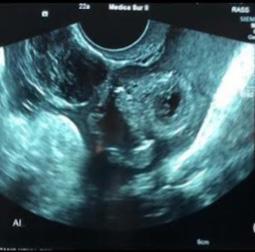

Mujer de 22 años, primigesta, sin antecedentes de importancia, quien acude a la consulta externa de ginecología por presentar dolor abdominal de moderada intensidad de inicio súbito acompañado de nausea y vómito. Previo a este cuadro refiere sangrado menstrual hace un mes y continuar con leve sangrado intermitente, así como ingesta de pastillas de emergencia a dosis de 1.5 mg entre 5-6 semanas previas al inicio de los síntomas sin especificar fecha exacta. Niega prueba de embarazo ni otros estudios de diagnóstico. A la exploración física se encuentran signos vitales dentro de parámetros normales, con dolor abdominal localizado en la fosa iliaca izquierda con rebote positivo y signos de irritación peritoneal, al tacto vaginal se evidencia escaso sangrado transvaginal, con cérvix posterior cerrado. Se realiza ultrasonido transvaginal encontrando el útero en anteversión, con medidas de 7.5 x 4.2 x 5.7 cm, endometrio heterogéneo con grosor de 19.1 mm, sin evidencia de saco gestacional intrauterino; ovario izquierdo con imagen quística compleja, imagen anecoica ecogénica que muestra vascularidad periférica a la exploración Doppler color, el ovario derecho no se delimita parcialmente definido con heterogeneidad del anexo, con presencia de abundante líquido libre en fondo de saco posterior con ecos internos que sugieren material hemático.(figuras 1-2)

Figura 2. Anexo izquierdo con imagen quística compleja.

Figura 1. Liquido libre en fondo de saco posterior.